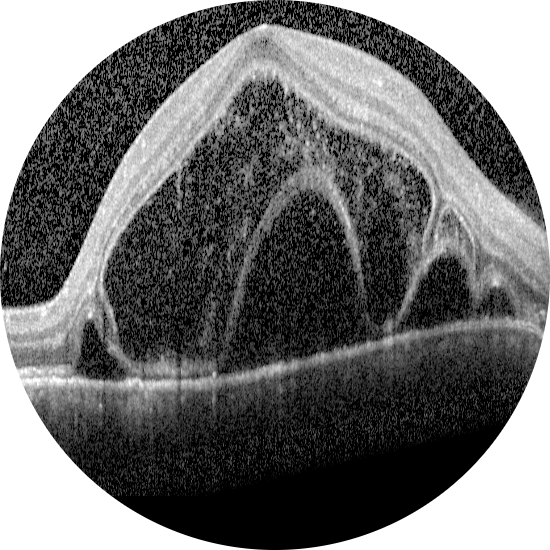

2026 Şubat Ayın Videosu

Retina dekolmanı cerrahisi sırasında perflorokarbon sıvı uygulaması esnasında ge ...